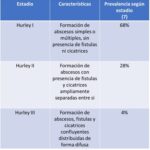

Respecto de los diagnósticos diferenciales, en las etapas iniciales la HS debe distinguirse del acné, ántrax, forúnculos, quiste dermoide, erisipela, quistes epidermoides, abscesos peri-rectales y quistes pilonidales. En la etapa tardía, las enfermedades a diferenciar son actinomicosis, fístulas anales, enfermedad de Crohn, enfermedad por arañazo de gato, granuloma inguinal, linfogranuloma venéreo, nocardiosis, TBC, tularemia, pioderma gangrenoso, entre otros. Para la clinimetría se emplean diferentes escalas, como la Hurley, Sartorius, entre otras. Estas permiten clasificar la HS según su gravedad y además objetivar su evolución clínica y la respuesta terapéutica. Sin embargo, el método de Hurley no es adecuado para evaluar la respuesta terapéutica, ya que este es estático, no cuantitativo y no tiene en cuenta la actividad inflamatoria, aunque es útil para decidir una eventual intervención quirúrgica. A pesar de todo, en Argentina se exige como estándar para la prescripción terapéutica. El estadio I se corresponde con HS leve, consistente en abscesos únicos o múltiples sin cicatrices ni fistulas. Los estadios II y III se corresponden con las formas moderadas y graves; el estadio II se caracteriza por la presencia de uno o más abscesos recurrentes con formación de fistulas y cicatrices y el estadio III, por iguales lesiones, pero que afectan toda una región anatómica.